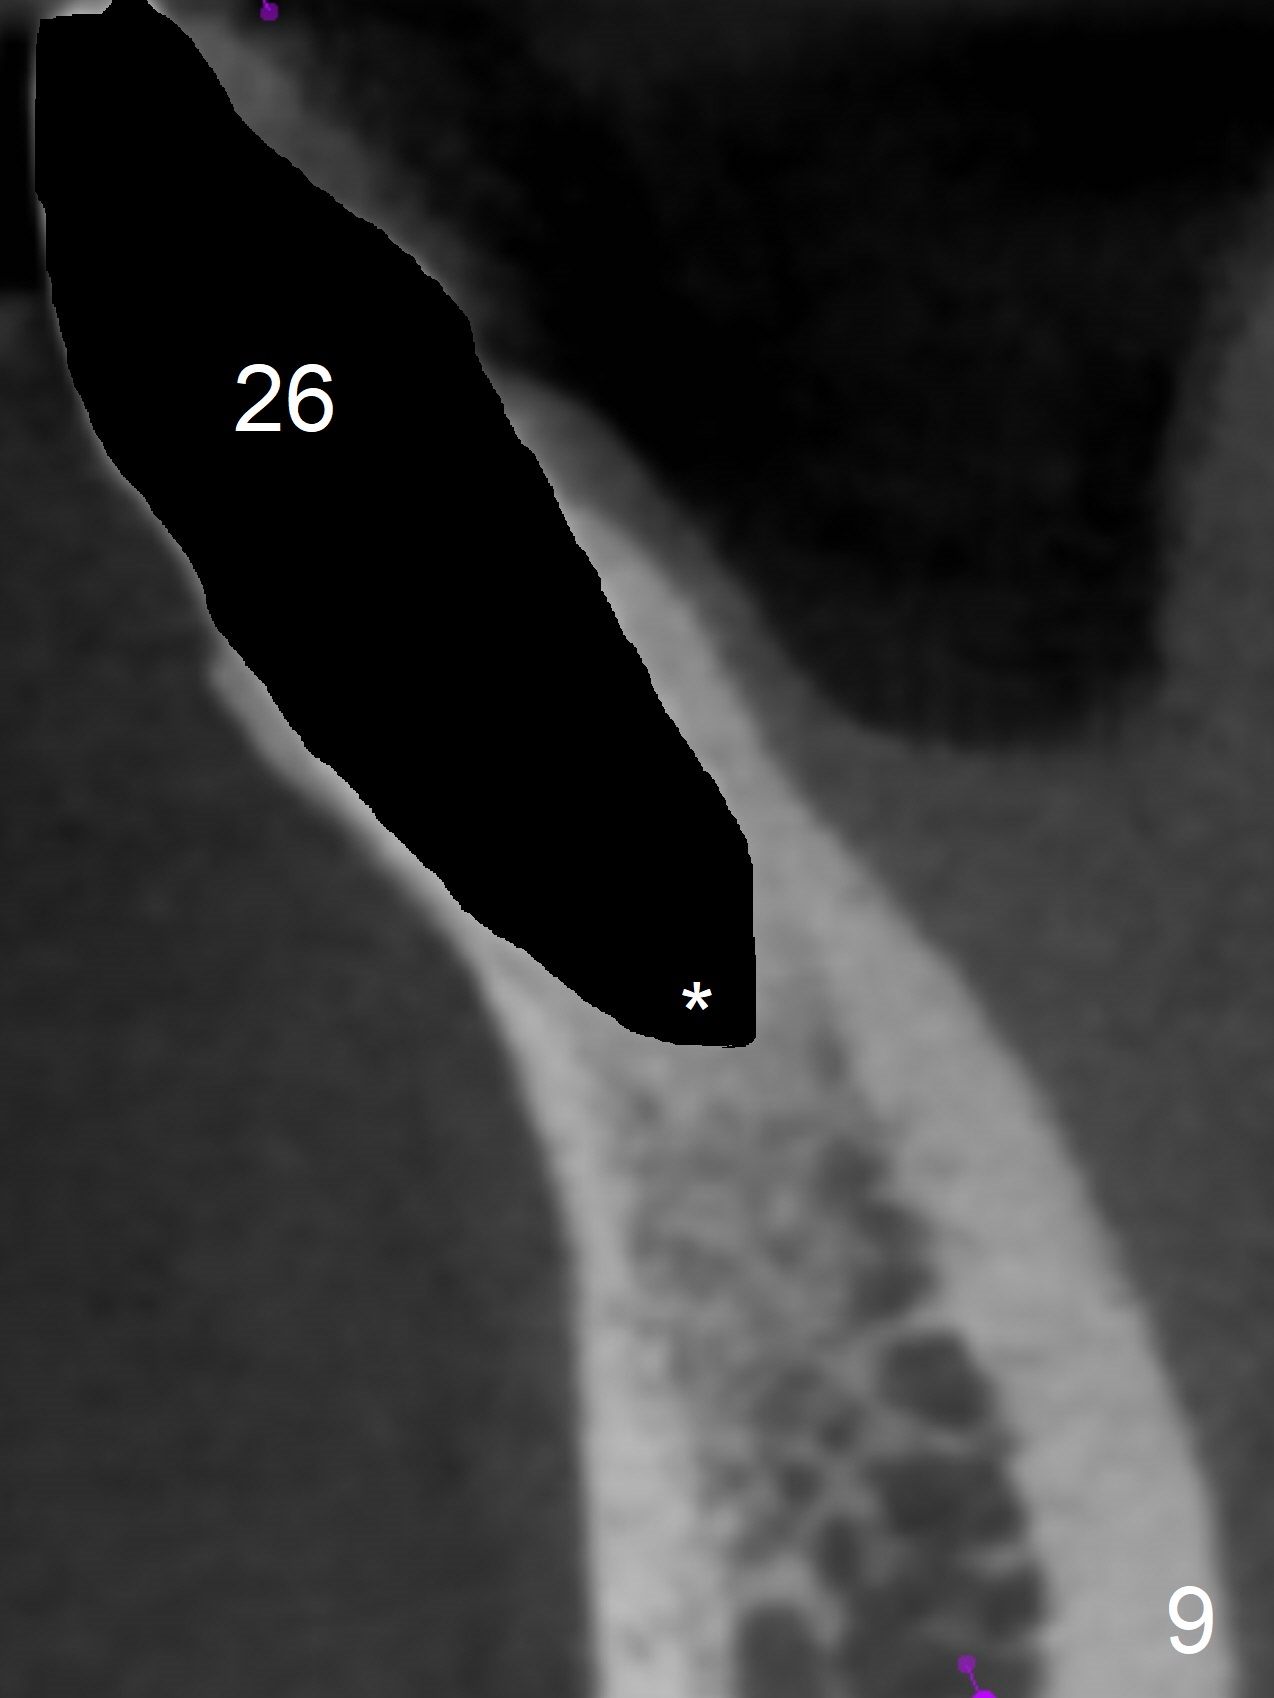

In fact the apex of the lateral incisor is also in the center of the alveolus (Fig.9 *). Osteotomy established in the lingual slope for a long distance (Fig.10,11) will perforate the lingual plate. The correct method of osteotomy is to set up in the middle of the socket and along the long axis of the alveolus with 2 fingers holding the alveolus (Fig.12 (2 circles)). The problem for this case is to use the lower RPD as a guide. With the RPD in place, the tactile sensation is lost.